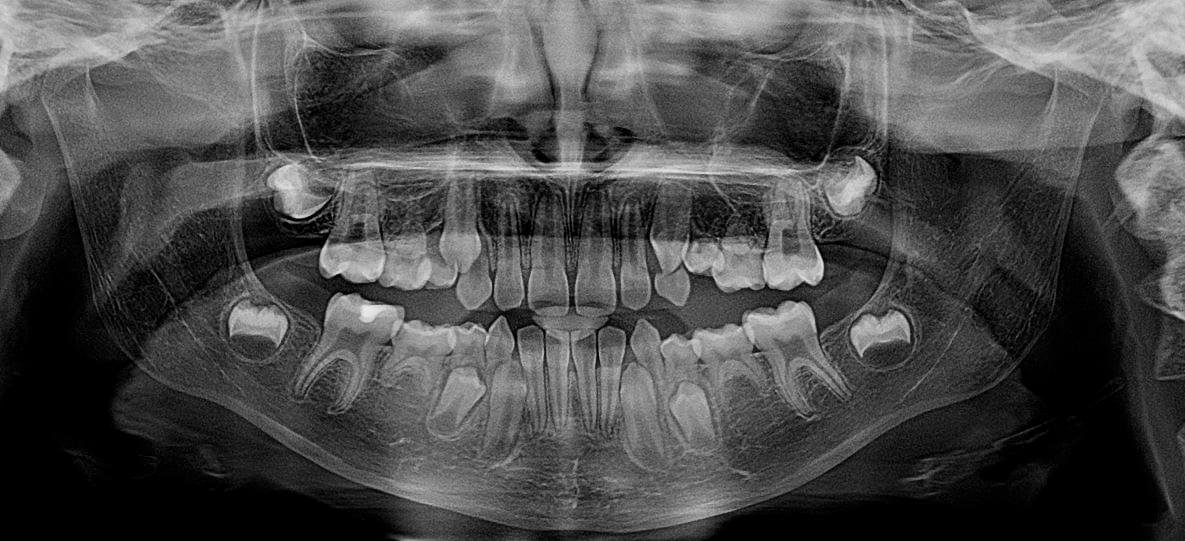

✍ Недоліки Ортопантомограми (ОПТГ):

Хоча Ортопантомограма (ОПТГ) є чудовим і швидким інструментом для загального огляду, вона має суттєві недоліки порівняно з більш сучасними методами, як-от КТ щелеп.

● Накладання структур (проекційні викривлення):

Це плоский (2D) знімок тривимірного об'єкта. Оскільки все, що знаходиться на шляху

рентгенівського променя, проєктується на одну площину, деякі важливі структури можуть

накладатися одна на одну. Наприклад, ви можете не побачити невелику кісту чи прихований

карієс через накладання сусідніх зубів або щелепних кісток.

● Геометричні та розмірні спотворення.

Зображення на ОПТГ ніколи не відповідає реальним розмірам 1:1. У

різних частинах знімка (особливо спереду та збоку) може бути різне збільшення або

спотворення. Це ускладнює точні виміри.

● Неточність вимірів:

Через спотворення, вимірювання на ОПТГ не є достатньо надійними для

складного лікування, такого як точне визначення довжини кореневого каналу або вибір розміру

імпланта.